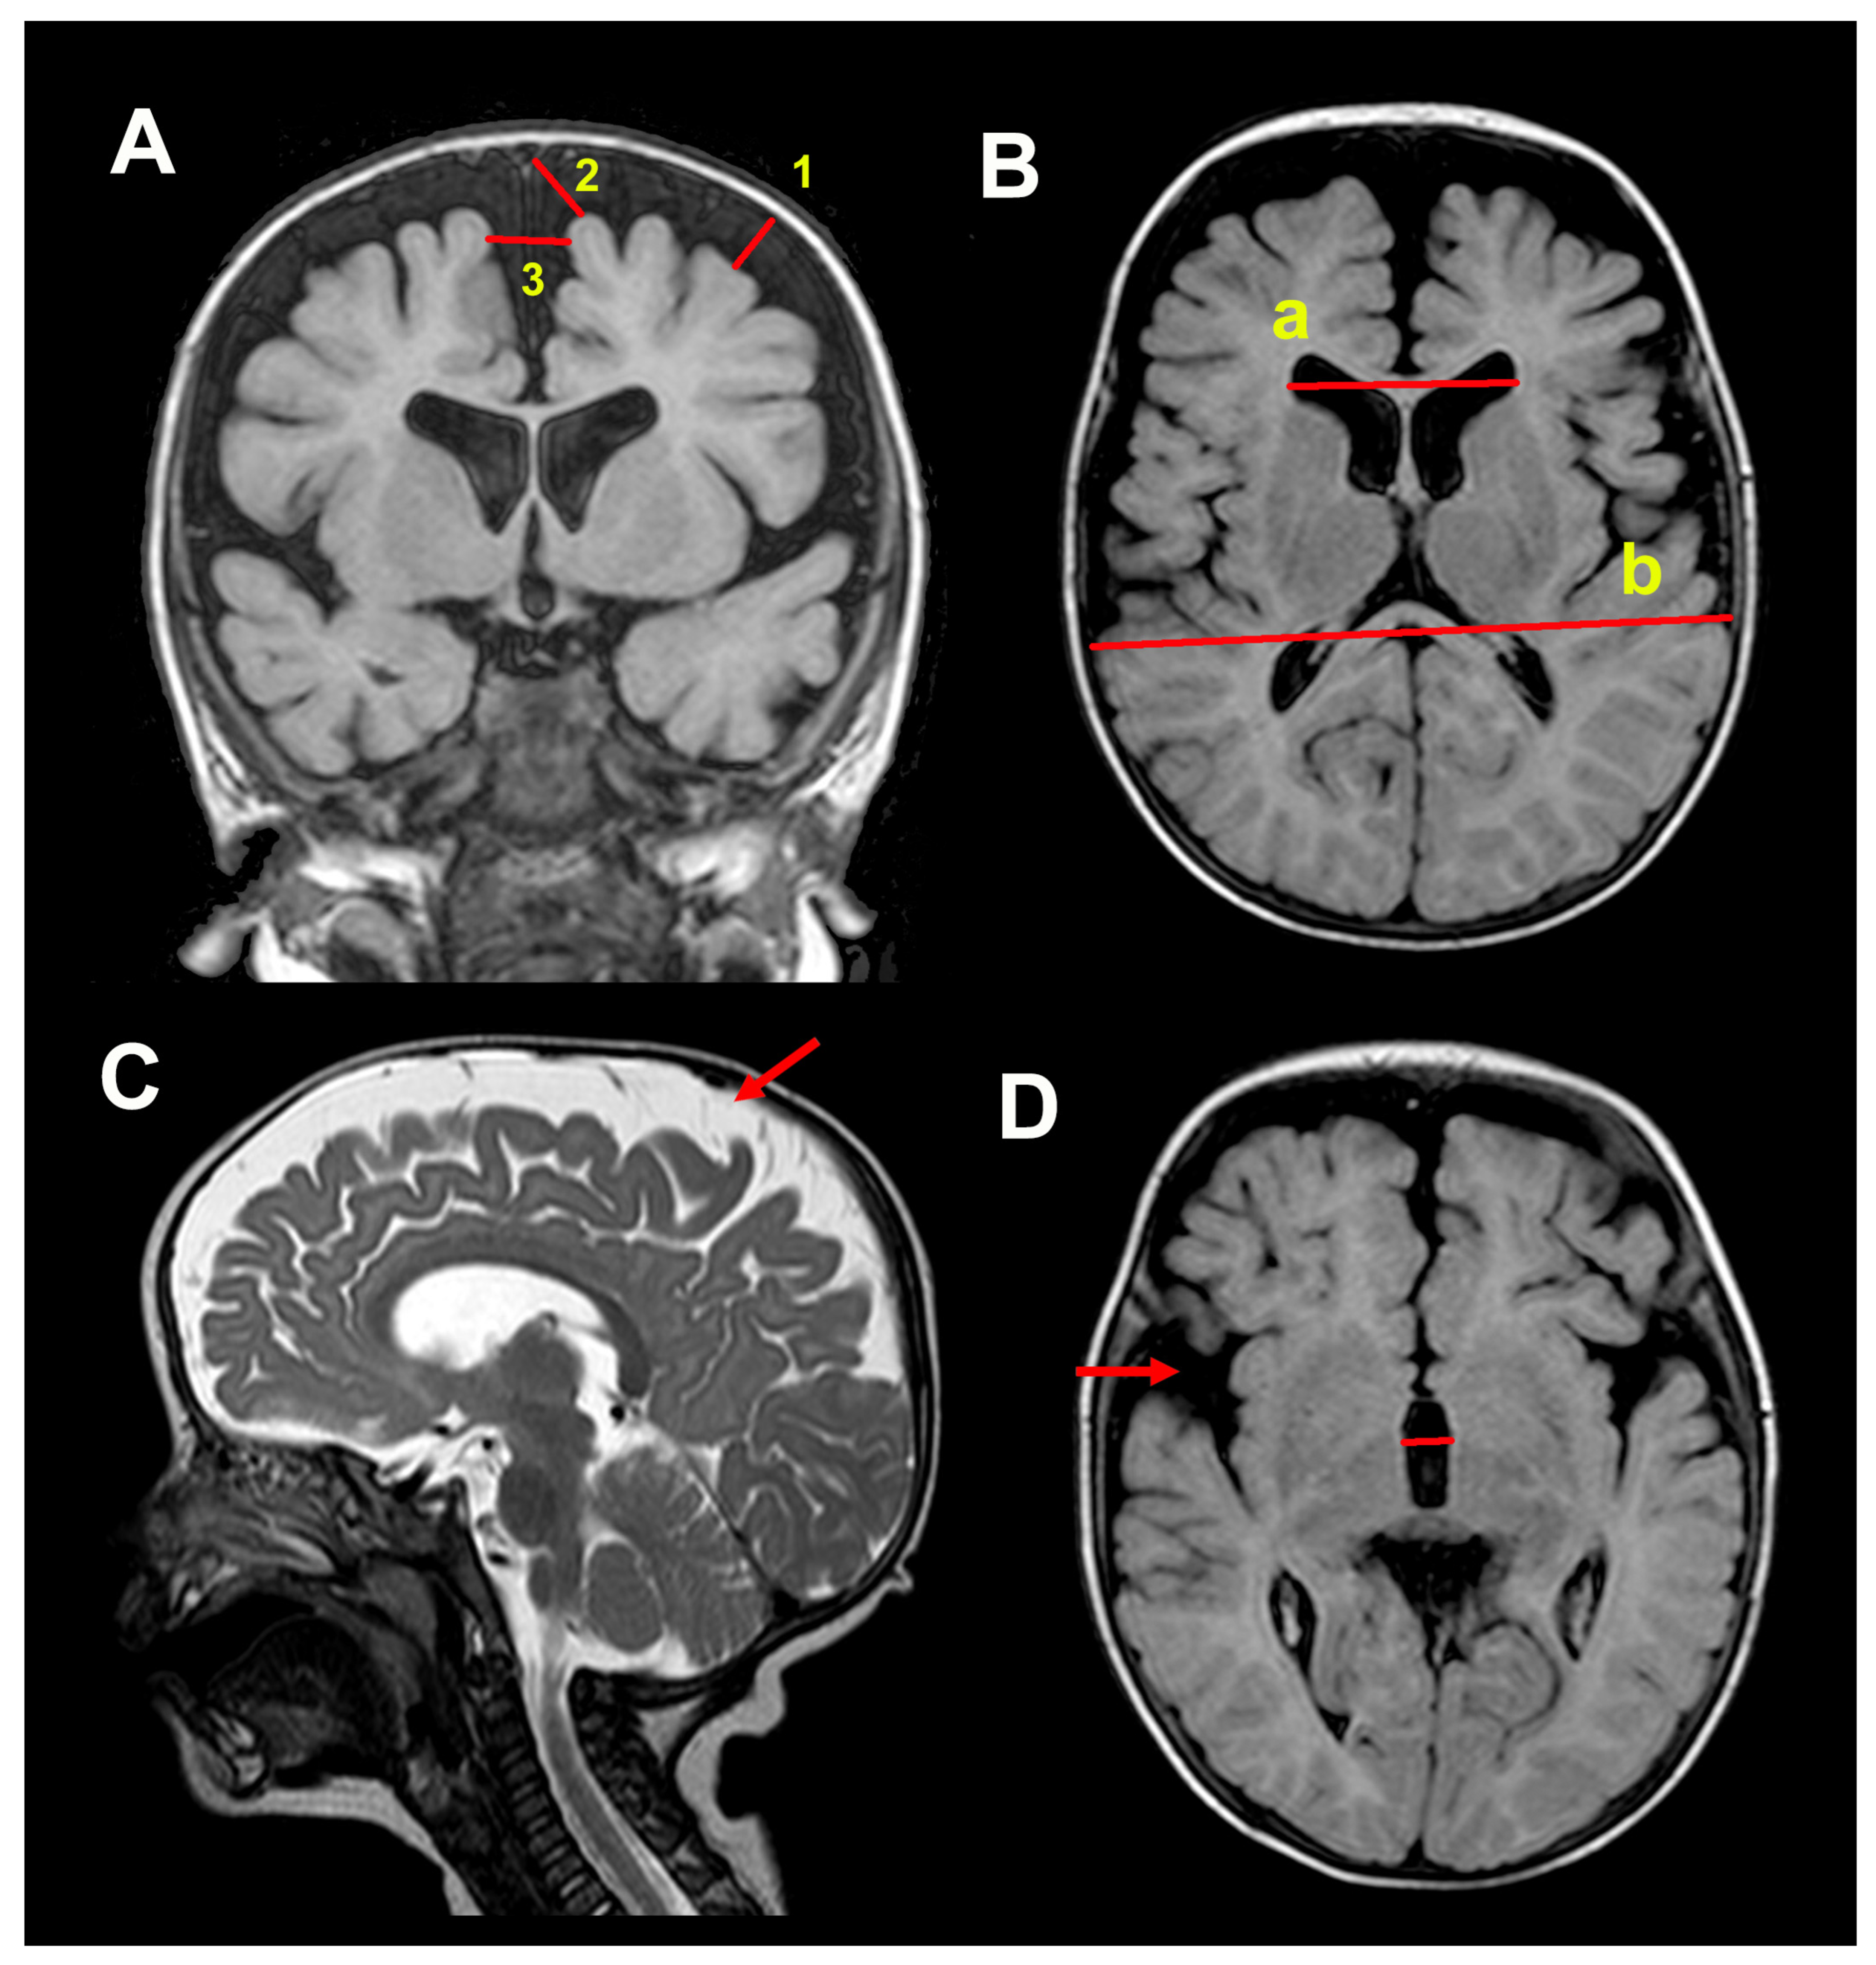

2.3. Neuroimaging Studies

3.2. Neuroimaging Data